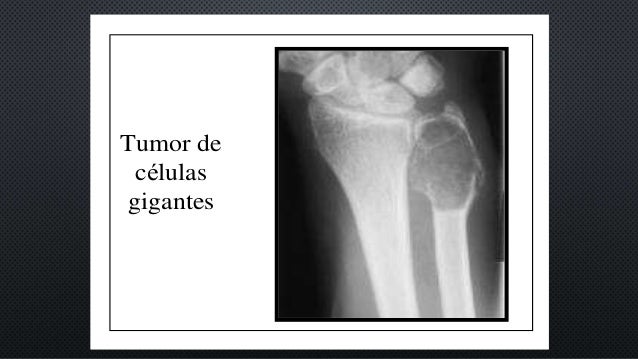

Tumor De Celulas Gigantes En Columna Vertebral